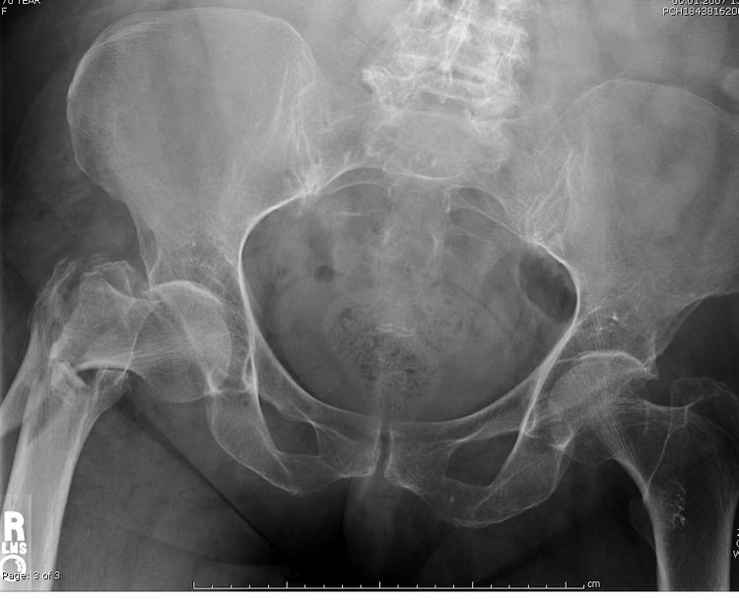

Здесь пара случаев фиксации похожих переломов:

первый высокоэнергетическая травма 36 лет

Djoldas Kuldjanov, M.D.

Department of Orthopedic Surgery

St. Louis University